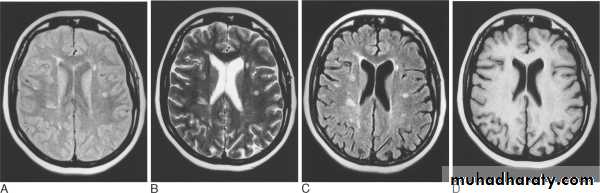

Patient with multiple sclerosis with plaques of demyelination shown on (A) fast spin-echo (FSE) proton density; (B) FSE T2; and (C) FSE FLAIR. There is no discernible abnormality on T1-weighted images without contrast